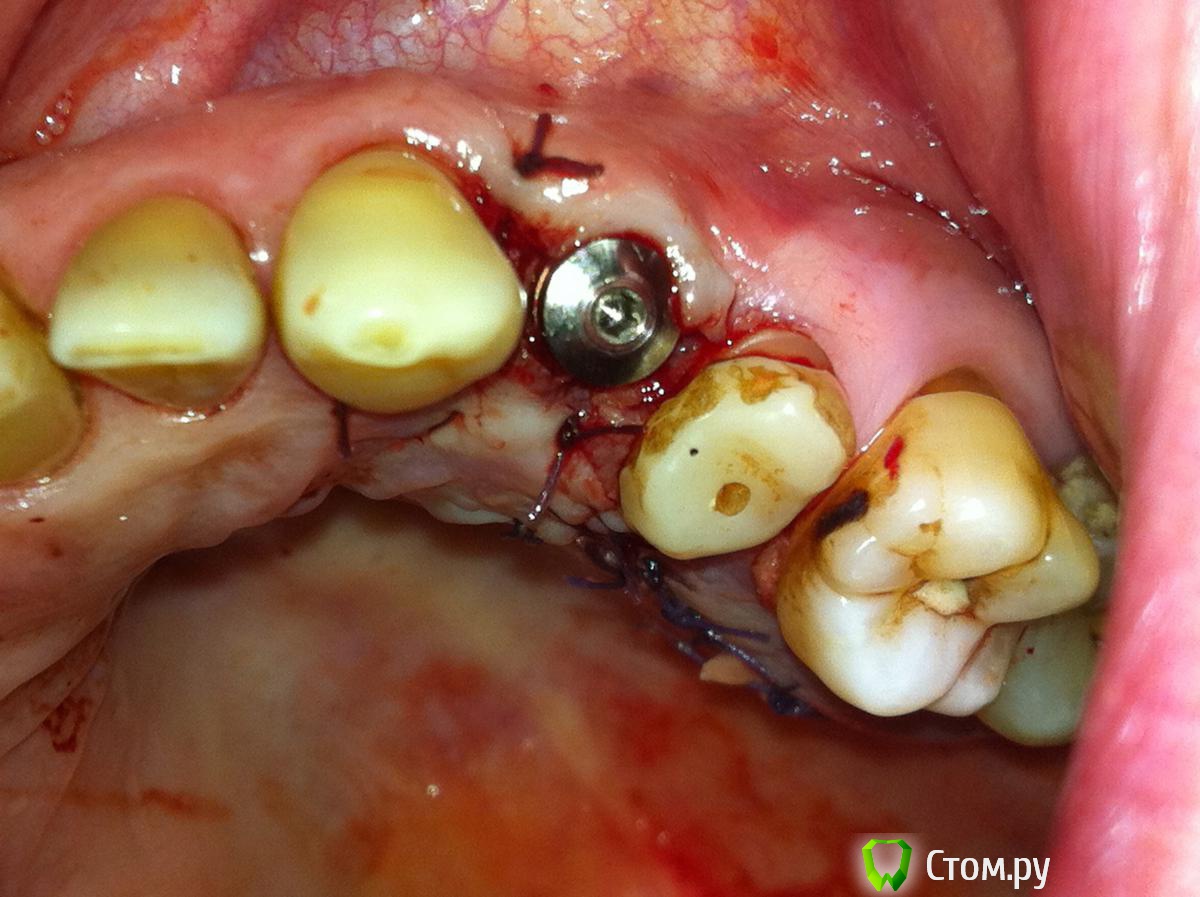

Tabula Rasa Опубликовано 29 сентября, 2014 Поделиться Опубликовано 29 сентября, 2014 (изменено) Пациент Л, 65 летИмплантация в области 2.4. Ожидание 4-4.5 месяца->недостаток мягких тканей и к тому же явный "завал" вестибулярного овала->ротированный лоскут на ножке одновременно фиксируемый формирователем->1 месяц->протезирование.Окончательным результатом не до конца доволен,т.к десна все равно усела и по высоте,и по ширине...думается ошибка в отсутствие временной коронки на импланте была. Изменено 29 сентября, 2014 пользователем IlyaPM Ссылка на комментарий

Alexey Doc Опубликовано 30 сентября, 2014 Поделиться Опубликовано 30 сентября, 2014 Мне тоже кажется что винт вестибулярно стоит Ссылка на комментарий

Дмитрий Никитюк Опубликовано 30 сентября, 2014 Поделиться Опубликовано 30 сентября, 2014 Мне тоже кажется что винт вестибулярно стоит Креститься нужно , а лучше штангенциркуль взять: http://s017.radikal.ru/i432/1409/a3/aa03dee0bb19.png Видно как топикстартер вышел за пределы эстетического окна. В таких условиях рассчитывать на суперрезультат не приходится. Но не смертельно. 9 Ссылка на комментарий